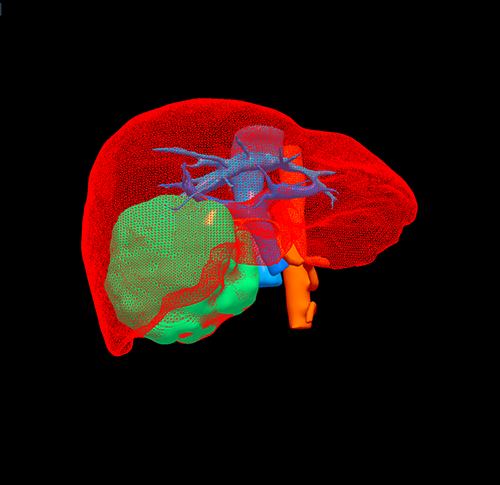

右肝癌----S567切除